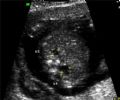

- Echogenic intracardiac foci